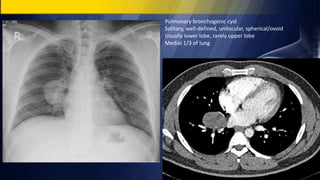

Pulmonary bronchogenic cyst

Solitary, well-defined, unilocular, spherical/ovoid

Usually lower lobe, rarely upper lobe

Medial 1/3 of lung

Pulmonary bronchogenic cyst Solitary,well-defined, unilocular, spherical/ovoid Usually lower lobe, rarely upper lobe Medial 1/3 of lung